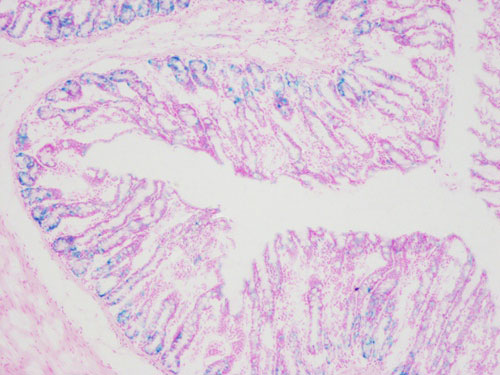

β-半乳糖甘酶染色,衰老細胞通常體積變會大,表達pH6.0時有高酶活性的β-半乳糖苷酶。染色中以X-ga1(5-溴-4-氯-3-吲哚-β-D-半乳糖苷)為底物,在衰老特異性的β-半乳糖苷酶催化下,半乳糖苷鍵被水解生成深藍色產物,光學顯微鏡下很容易觀察到變成藍色的表達β-半乳糖苷酶的細胞或組織。

β半乳糖甘酶染色-小鼠腸道

衰老細胞呈深藍色,細胞核紅色